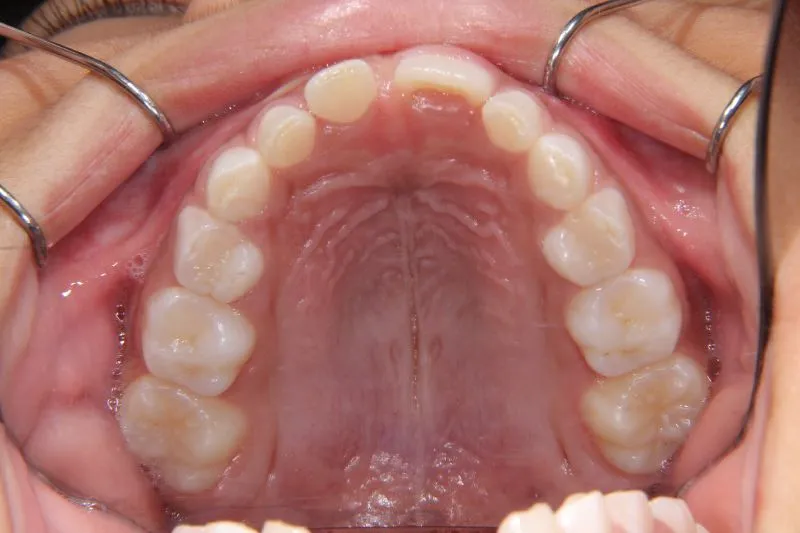

状態 前歯で噛めない(開咬/オープンバイト)

1.主訴 前歯がかみ合わない・出っ歯

2.診断名あるいは主な症状 開咬

4.治療に用いた主な装置 拡大床

前歯がかみ合っていません。

前歯は物を噛みちぎる(ハサミのような)役割をするのですが、歯と歯が離れていて本来の役割を果たしていません。